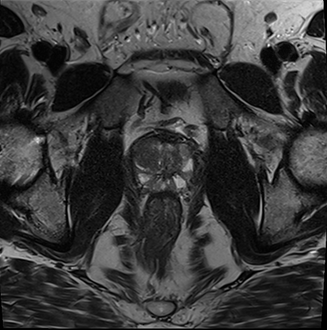

Prostata-MRT

Dabei spielt die multimodale Prostata-MRT die zentrale Rolle und ist herkömmlichen Vorsorgemethoden wie dem Tastbefund, der Ultraschalluntersuchung oder der Bestimmung des Prostata-spezifischen Antigens (PSA-Wert) aus einer Blutprobe überlegen. Dabei kommen verschiedene Techniken zur Darstellung der Anatomie, der Zelldichte und der Gefäßversorgung der Prostata zum Einsatz. Die Prostata-MRT gilt daher zurzeit als das sensitivste radiologische Verfahren einen Tumor zu entdecken, wobei ein unauffälliges MRT die Erkrankung mit hoher Sicherheit ausschließt. Dadurch können eventuell unnötige diagnostische und therapeutische Eingriffe verhindert werden. Die Prostata-MRT ist eine aufwändige und technisch anspruchsvolle Untersuchung und liefert nur in der Hand von Experten verlässliche und reproduzierbare Ergebnisse. Wichtig ist der Einsatz moderner Techniken, wie sie von den Fachgesellschaften für Urologie und Uroradiologie im Rahmen der sogenannten „multiparametrischen MRT" (mpMRT) gefordert werden. Die Begutachtung erfolgt gemäß der sogenannten PI-RADS-Kriterien („Prostate Imaging Reporting and Data System") in ihrer aktuellen Version.